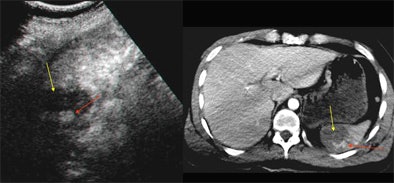

| Contrast-enhanced ultrasound (left) and contrast-enhanced CT (right) of the spleen. Oblique sonogram shows a large deep hypoechoic area of splenic laceration (yellow arrow) with internal hyperechogenicity due to contrast medium pooling (red arrow). The CE SSCT shows similar findings, confirming the injured area (yellow arrow) and the contrast leakage (red arrow). All images courtesy of Dr. Bianca Cusati. |